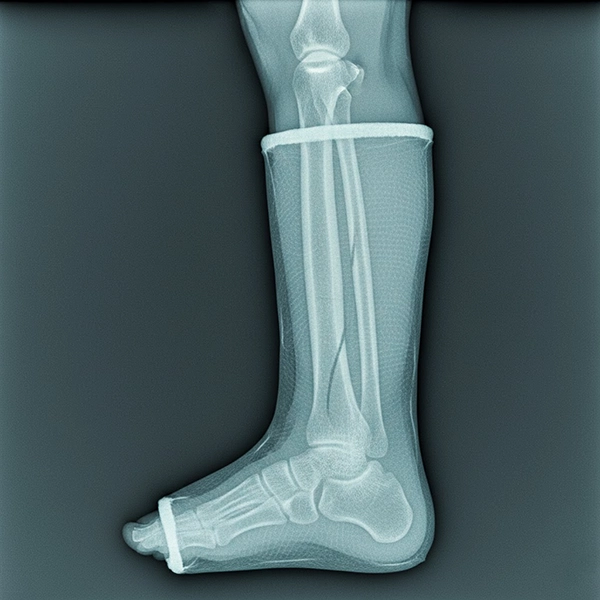

نمای رادیولوژی از اندام گچ‌گیری‌شده با باند فایبرگلاس که جزئیات استخوان را با شفافیت بالا نشان می‌دهد

X-ray: باند فایبرگلاس در رادیوگرافی ساده، در قیاس با POP، شفافیت بالاتری ارائه می‌دهد. این یعنی خطوط شکستگی، پیچ و پلاک‌ها و کالوس‌سازی زودتر و بهتر دیده می‌شوند. کیفیت لبه‌گیری و یکنواختی لایه‌ها در کاهش خطوط مزاحم بسیار موثر است.